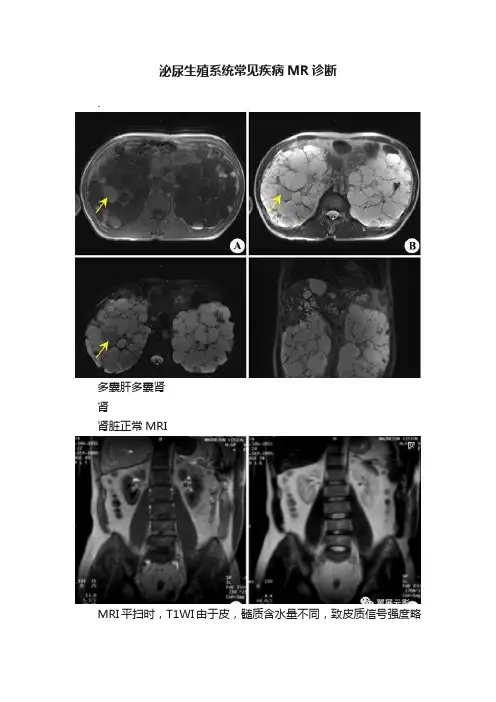

泌尿生殖系统常见疾病MR诊断.多囊肝多囊肾肾肾脏正常MRIMRI平扫时,T1WI由于皮,髓质含水量不同,致皮质信号强度略高于髓质,皮髓质分界清晰,T2WI肾皮,髓质均呈较高信号而分辨不清,肾窦脂肪组织在T1WI和T2WI上信号均较高,肾血管由于流空效应而无信号,GD-DTPA增强检查表现类似CT增强,正常MRU表现与正常IVU类似,可多角度观察。

MRI显示双肾的位置,大小,轮廓及信号正常,T1WI皮髓质分界清晰,MRU可显示集尿系统的正常形态表现,肾盂肾盏无积水扩张,输尿管常为断续显影,为其蠕动并无完全充盈尿液所致,膀胱充盈良好时边缘光滑,增强多期扫描强调两侧皮质强化,实质强化的同时性和明显强化的特征,肾盂期集尿系统内有造影剂充盈。